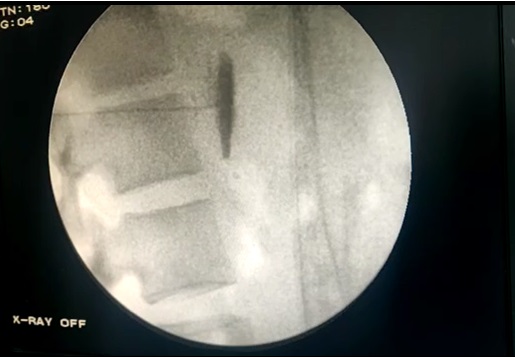

Τι είναι η Κυφοπλαστική και η Σπονδυλοπλαστική

Πρόκειται για ελάχιστα επεμβατικές θεραπείες, οι οποίες εκτελούνται με διαδερμική προσπέλαση και ενδείκνυνται για τη θεραπεία του πόνου σε ασθενείς με οστεοπορωτικά και παθολογικά κατάγματα των σπονδύλων από μεταστατική καρκινική νόσο. Η κυφοπλαστική αποκαθιστά το ύψος του σπονδύλου με χρήση ειδικού μπαλονιού και εισαγωγή τσιμέντου, ενώ η σπονδυλοπλαστική αφορά σε απλή εισαγωγή τσιμέντου στον καταγματικό σπόνδυλο. Και οι δύο τεχνικές γίνονται μέσω ειδικών trocar που εισάγονται διαδερμικά υπό ακτινοσκοπικό έλεγχο στους αυχένες των σπονδύλων και προωθούνται στο σπονδυλικό σώμα, όπου γίνεται η έγχυση του τσιμέντου ταχείας πήξης. Το τσιμέντο σταθεροποιεί τον σπόνδυλο και αποτρέπει την ανάπτυξη κύφωσης στα πάσχοντα σημεία.

Η κυφοπλαστική επιλέγεται για πρόσφατα κατάγματα (έως 6 μηνών). Και οι δύο τεχνικές μπορούν να εφαρμοσθούν σε πολλά επίπεδα της σπονδυλικής στήλης. Έχουν μικρό ποσοστό επιπλοκών και προσφέρουν άμεση ανακούφιση από τον πόνο και ταχεία αποκατάσταση του ασθενούς. Χρειάζονται νοσηλεία μιας μέρας. Σε ασθενείς υψηλού κινδύνου γίνεται να ολοκληρωθούν με μέθη και όχι γενική αναισθησία.